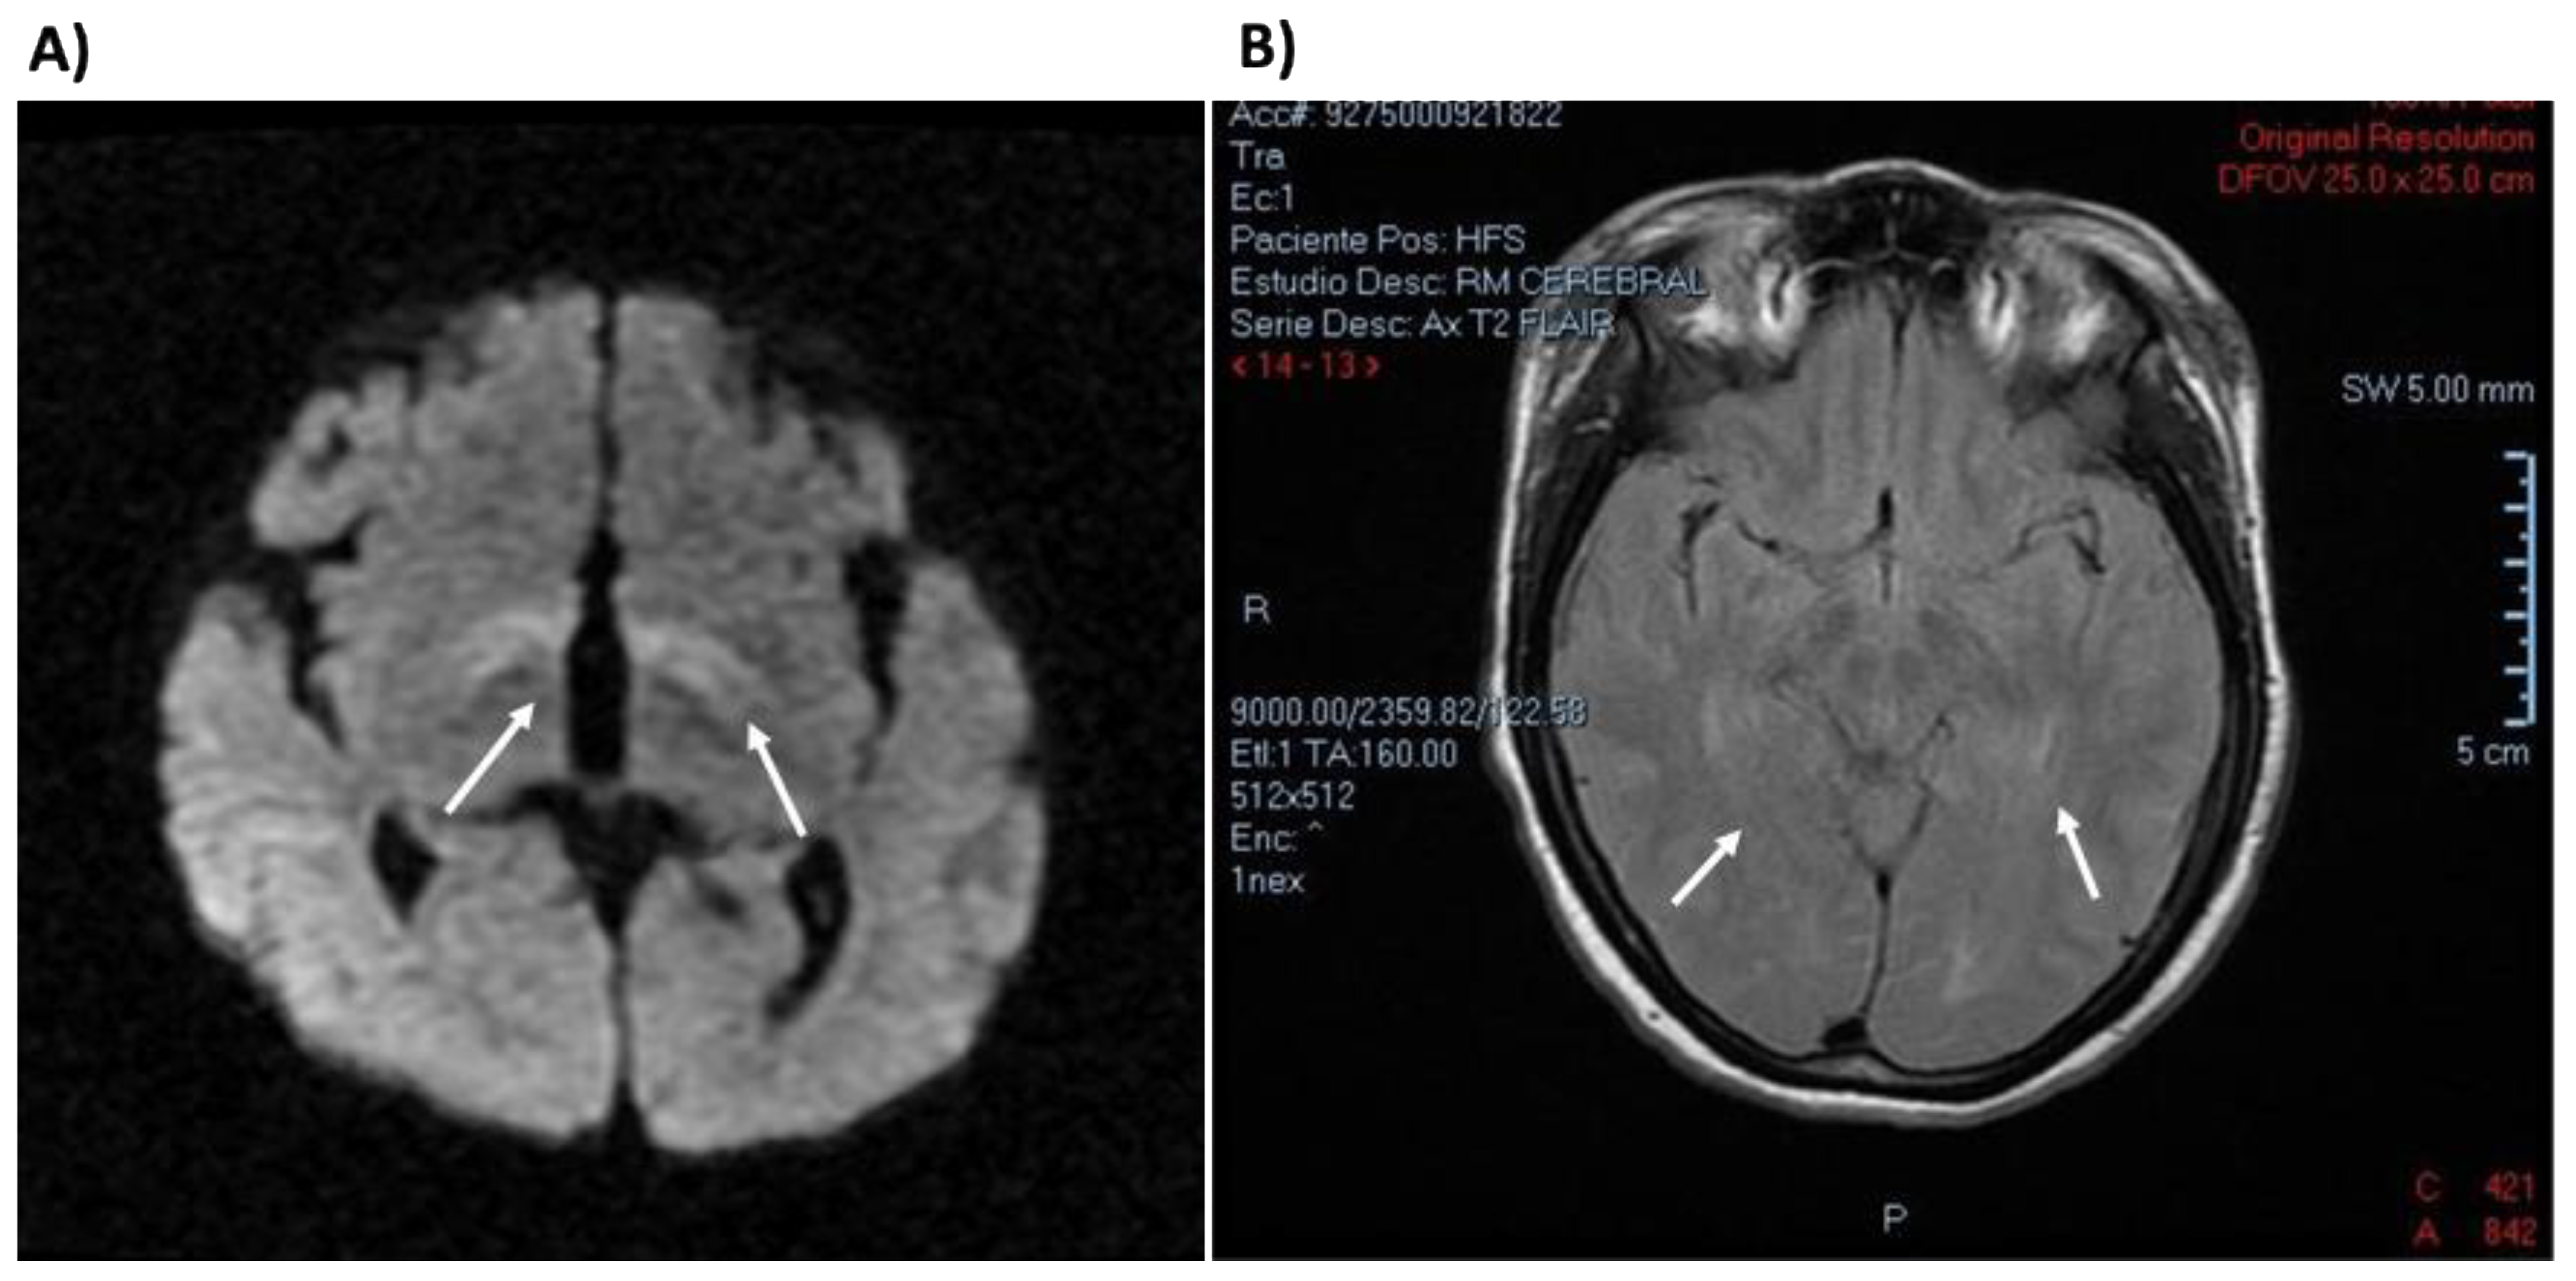

- Jiménez-Pérez, M.O.; Gómez-Garza, G.; Fernández-Lainez, C.; Ibarra-González, I.; Vela-Amieva, M.; Ruiz-García, M. Resonancia magnética nuclear de encéfalo en pacientes con fenilcetonuria diagnosticada tardíamente. Acta Pediátrica México 2015, 36, 9. [Google Scholar] [CrossRef][Green Version]